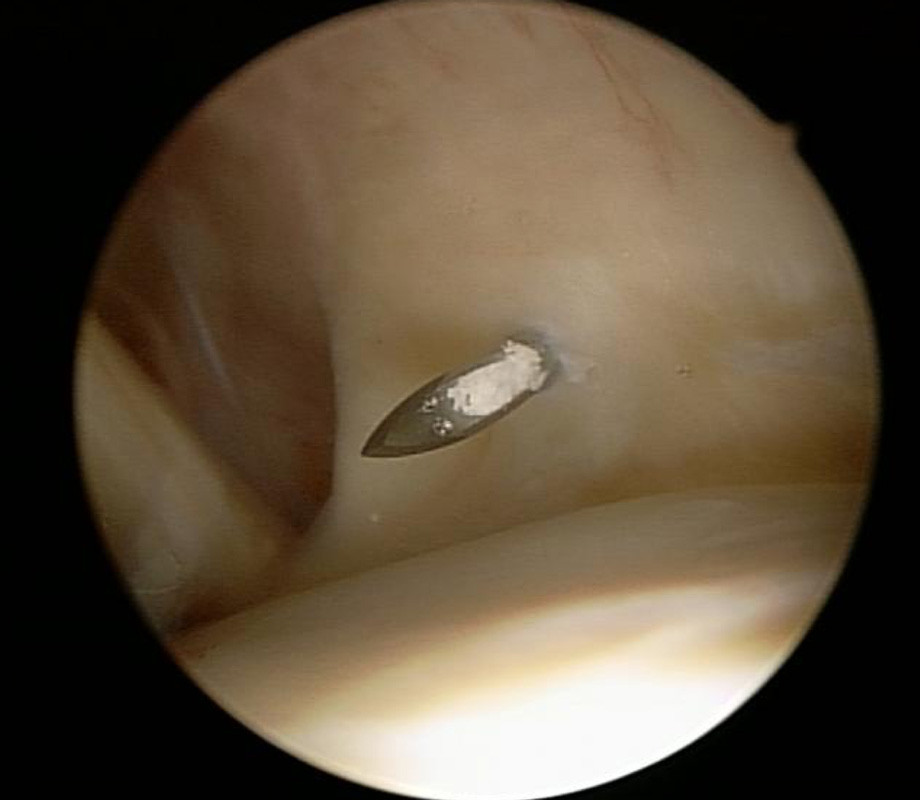

Der in der Sehne gelegene Kalkherd wird mit einer Hohlnadel (Bild 2) (der Kalk bleibt in der Nadelöffnung hängen) lokalisiert, danach wird der Kalk nach Eröffnung der betroffenen Sehne mit einem Löffel (Bild 3) möglichst vollständig entfernt und abgesaugt.